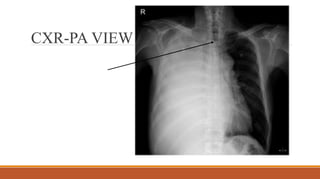

CXR-PA VIEW